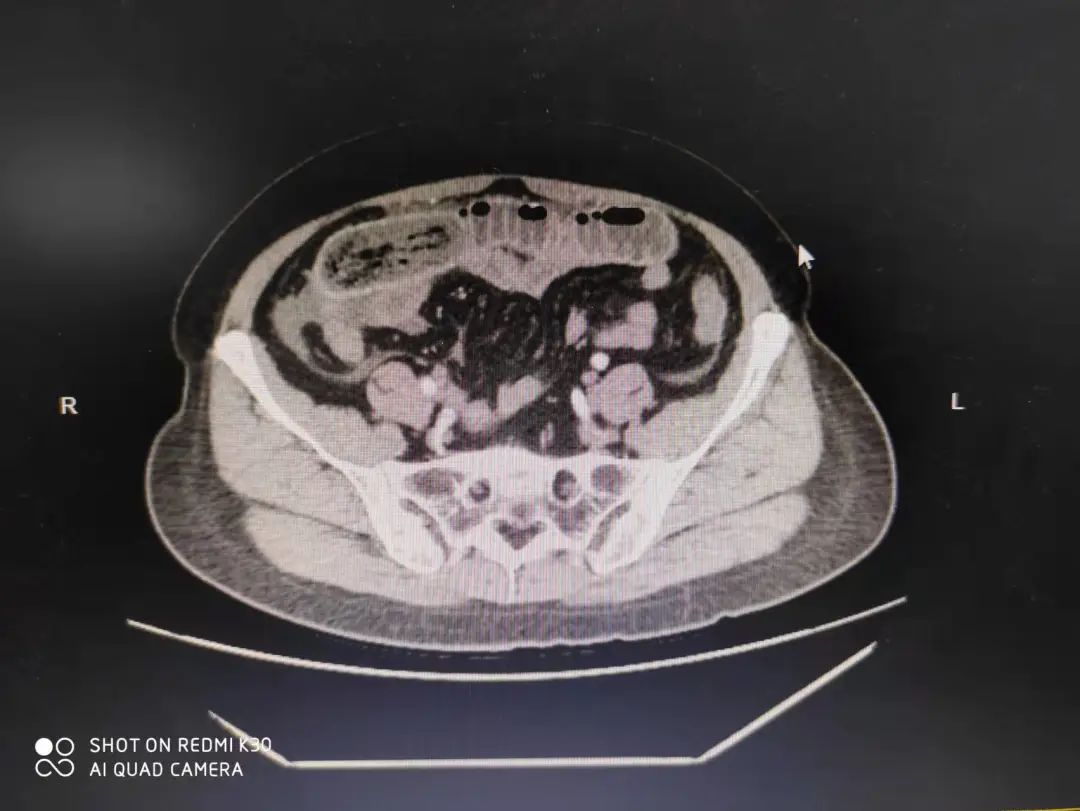

“我院病区前几日就收治了一名56岁的女性,因三天前食用竹笋后出现上腹胀痛,初期未重视,未治疗。后期疼痛逐渐加重,伴随恶心呕吐,肛门停止排便、排气,饮食也减少。经过腹部CT检查提示空肠上段粪便梗阻,血常规提示感染严重,我院急诊拟‘肠梗阻’收治住院。入院后经过科室讨论决定,实施腹腔镜探查以及手术,发现堵塞物为半根未消化的竹笋,取出异物,手术顺利结束,目前患者身体正在恢复中。”据我院外科医生杨京茹介绍,春笋含有丰富的粗纤维,比较难消化,大量食用会刺激肠胃,损害胃黏膜。如果出现胃胀、胃痛,肛门停止排便、排气,需要立即就医。